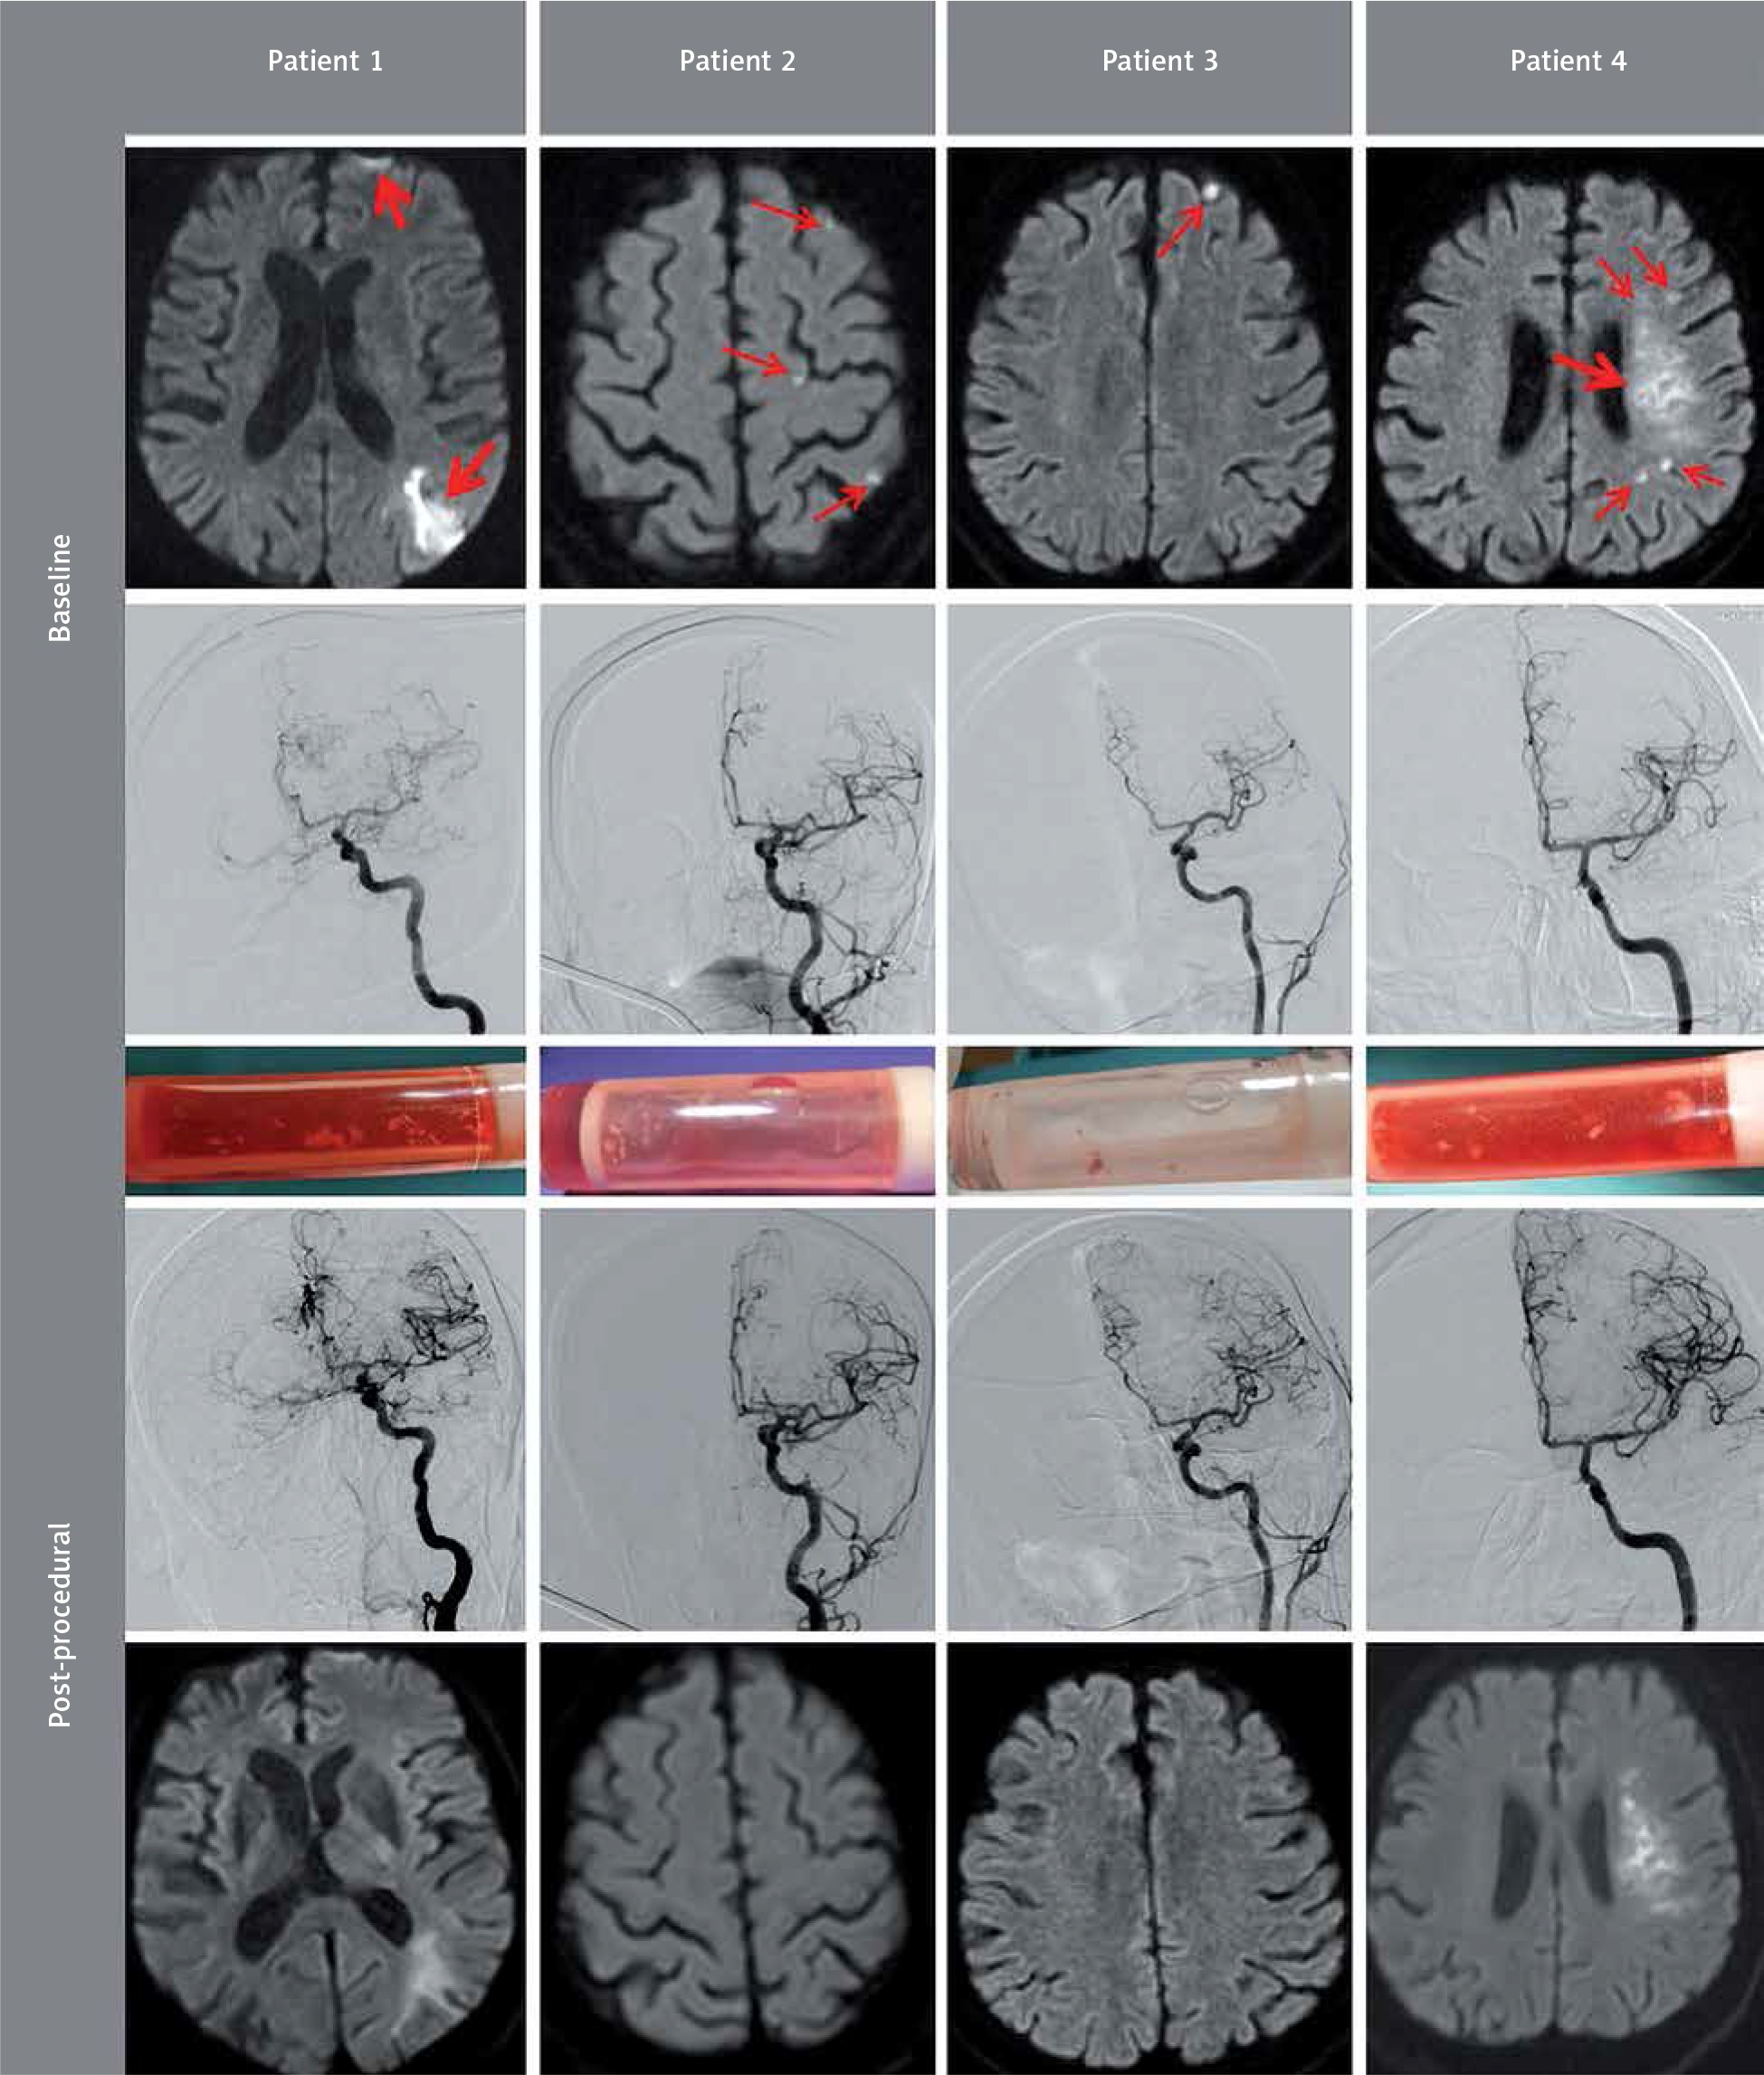

Figure 2

Angiography, cerebral ischemia imaging, and the flow reversal filter material in transcervical carotid artery stenting under flow reversal. A – Angiography at fundamental stages of the procedure. The top panel shows baseline angiographic images after establishing vascular access (cf. Figure 1) in four consecutive patients with sub-acutely symptomatic internal carotid artery stenosis (Duplex images were consistent with a thrombus-containing tight ICA lesion in all subjects, Patient 1 had a tandem stenosis). All patients are left-hemispheric dominant, and the symptom-causing lesion was in the left internal carotid artery (LICA). Two patients (Patient 1 and Patient 4) presented with subacute (≤ 14 days) left-hemispheric stroke (cf. Figure 2 B); two other subjects had crescendo TIAs that were presumed to be hemodynamic due to a very high lesion severity on Duplex imaging (baseline diffusion-weighted imaging provided evidence for concomitant spontaneous plaque embolism, cf. Figure 2 B). The second panel from the top illustrates lesion crossing and predilatation under flow reversal (red arrows). CCA clamping was endovascular in Patient 1 and Patient 4 (see inflated CCA balloons in the bottom of the images in Patient 1 and Patient 4, FlowGate and MoMa, respectively) and surgical (tourniquet; cf. Figure 1) in Patient 2 and Patient 3. In all cases the guidewire was WhisperMS 0.014’. Predilatation (insets) was performed using coronary balloons of 3.5 mm, 3.5 mm, 4.0 mm and 3.0 mm, respectively at 10–12 atm. Backward washout of the contrast upon lesion predilatation (compare images in the third panel with those in the second panel) is consistent with an effective spontaneous transport of any debris to the filters that are shown in Figure 2 B. The second panel from the bottom shows stent placement and implantation under continued flow reversal (CGuard 9.0 × 40 mm, CGuard 9.0 × 30 mm, CGuard 10.0 × 30 mm, and CGuard 9.0 × 30 mm respectively), as well as (insets) sequential post-dilatation optimizations of the stents that we perform routinely (6.5 mm balloon in Patient 1, 6.0 mm balloon in Patient 2, and 5.5 mm balloon in Patient 3 and Patient 4). Final angiographic results of the procedures are demonstrated in the bottom panel, consistent with a full, optimal endovascular reconstruction of the lumen of the artery with 0% residual stenosis in all cases, full patency of the branches, and a full respect of the anatomy (note the SmartFIT characteristics of the stent – self-adjustment of the widely open nitinol frame, with an adequate ‘self-tapering’ in case of a significant ICA/CCA diameter mismatch – best illustrated in Patient 3, alleviating a need for any ‘tapered’ versions of the device; for the final stent images see the insets). B – Cerebral imaging at the point of subacute clinical symptoms triggering referrals for revascularization, and the post-procedural controls. The top panel is diffusion-weighted magnetic resonance (DW-MRI) cerebral imaging at the point of symptoms that triggered intervention (revascularization was, in all cases, within 14 days), illustrating acute/subacute lesions in all patients. Small embolic foci are depicted with thin arrows whereas thick arrows indicate relatively large ischemic zones that were consistent with clinically significant, lasting stroke symptoms. The second panel from the top shows cerebral angiography prior to the symptomatic carotid artery revascularization (injections directly via the CCA sheath). Patient 1 (a physician) had undergone a symptomatic occlusion of the right internal carotid artery 4 years earlier. The middle panel shows post-procedural photographs of the filters that were part of the flow reversal temporal arteriovenous fistula (shunt) circuit in these patients (cf. Figure 1). Flow reversal, as our default procedure strategy in such patients, taken together with the lesion ‘no touch’ strategy until flow reversal establishment, enabled a 100% effective protection of the brain against the plaque material in all subjects (see control cerebral images in the bottom for comparison with the baseline images). Absence of any new post-procedural lesions on DW-MRI images is consistent with an effective capture of all embolic debris in the filters. The fourth panel from the top is post-procedural cerebral angiograms that are consistent with a normalized ipsilateral cerebral supply in all cases (in Patient 1 note also a marked improvement of the collateral supply to the right hemisphere). The bottom panel presents control DW-MRI images that were acquired within 3-10 days after revascularization. In Patient 4, 1.5T scanner was used for baseline DW-MRI imaging whereas the control scan was performed with 3T (the 1.5T scanner was not operational at the point of control imaging). Note that optimal intraprocedural cerebral protection by transient flow reversal, combined with an effective plaque containment by the MicroNET-covered second-generation carotid stent (embolic prevention) resulted in a total absence of peri-procedural cerebral embolism that is an established surrogate for peri- and post-procedural stroke risk in relation to the index lesion [35]

The filters used in the shunt contained embolic material in all cases (Figure 2 B). The embolic material capture was 100% effective as control DW-MRI scans (Figure 2 B) showed absence of any new embolism. There was a natural evolution of the cerebral index infarcts in Patient 1 and Patient 4 that had caused clinical stroke symptoms prompting urgent referral for carotid revascularization. The small embolic pre-procedural DW-MRI lesions in Patient 2, Patient 3 and Patient 4 were no longer detectable on the control scans (and they were also not visible on control FLAIR imaging). Evaluation of cerebral flow evolution in relation to DW-MRI imaging confirmed a combination of embolic and hemodynamic cerebral injury as mechanisms underlying presenting symptoms [25]. Thus the embolic debris collected in filters (Figure 2 B) confirmed the highly emboligenic characteristics of the carotid plaques in the study patients as indicated by the clinical characteristics (highly symptomatic lesions) and the Duplex and angiographic lesion imaging in relation to the baseline cerebral DW-MRI scans (Figure 2). Neurologic examination at 24–48 h post-procedurally revealed no new deficits. On day 3 or 4 post-procedurally the patients were discharged home (Patient 1, Patient 2 and Patient 3) or to a stroke rehabilitation centre as pre-arranged by the referring hospital (Patient 4). Discharge Duplex Doppler showed a normal stent lumen and normal in-stent velocities in all cases. Routine post-discharge evaluation was performed in the vascular surgery outpatient clinic at 10–14 days and was normal. Duplex and clinical follow-up, including neurologic examination, are scheduled at 30 days and then yearly. Follow-up DW-MRI examinations are scheduled at 90 days.